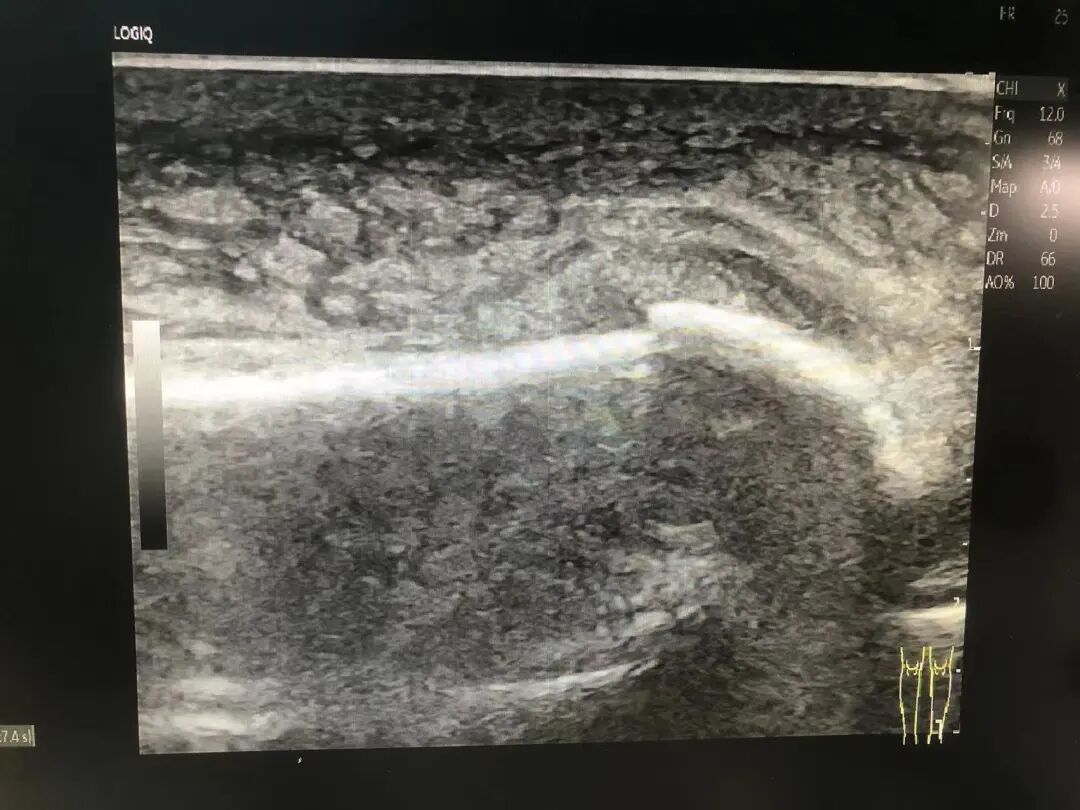

↑正中神经切割伤缝补术后再断裂